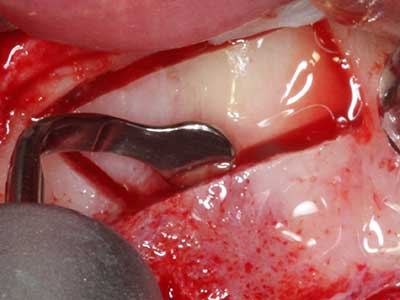

Bei der Knochenblockentnahme zeigen sich weitere Vorteile für die Piezochirurgie: Neben der bereits beschriebenen hohen Präzision bei der Osteotomie stellt sich gerade die Verwendung der dünnen Sägespitzen als besonders materialschonend heraus. Bei der Verwendung insbesondere von Lindemannfräsen sind mit deutlich höheren Entnahmeverlusten durch die dickere Instrumentenspitze zu rechnen (Lakshmiganthan, Gokulanathan et al. 2012). Die insbesondere bei retromolar entnommenen Blocktransplantaten notwendige basale Abtrennung wird durch speziell hierfür vorgesehene rechtwinklige Sägen erleichtert, so dass die Piezochirurgie als präzises, übersichtliches und sicheres Verfahren zur retromolaren Knochenblockgewinnung angesehen wird (Happe 2007) (Abb. 1-12).

Indikation: Bone Splitting